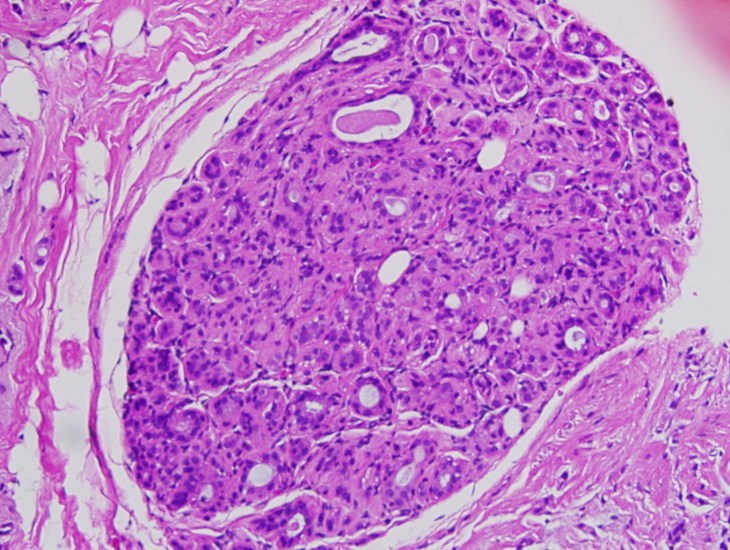

The authors identified 1328 cases from the total of 1822 that had the required tissue available for study and met other standard study criteria, and these represented the typical population of male breast cancers well in terms of type and grade and also how they were treated. Of these just under half – 613 – had a precursor lesion adjacent to the tumor and so available for study. Almost all of them (97.9%) were ductal carcinoma in situ (DCIS), as would be expected from men where almost all the tumors that present are invasive ductal carcinomas and where the breast tissue has ducts but only rudimentary lobules.

DCIS By Difu Wu (Own work) [CC BY-SA 3.0 (http://creativecommons.org/licenses/by-sa/3.0) or GFDL (http://www.gnu.org/copyleft/fdl.html)%5D, via Wikimedia Commons

The authors conclude that DCIS is commonly found next to invasive tumors in males with breast cancer, and is likely the precursor lesion.

This study provides solid evidence that invasive male breast cancers derive from DCIS lesions, as is the case for female breast cancers that are like them, i.e. invasive ductal carcinomas. Furthermore, the fact that the DCIS lesions share the ER/PR status and Her2 status with their adjacent aggressive descendants suggests that these characteristics are acquired early and may be driving early stages of tumor evolution. The same may be true of the gene mutations studied, but the numbers of samples where sequencing could be performed was small and the number of genes analyzed was also very small, and so a large study perhaps with better tissue collected prospectively needs to be done.